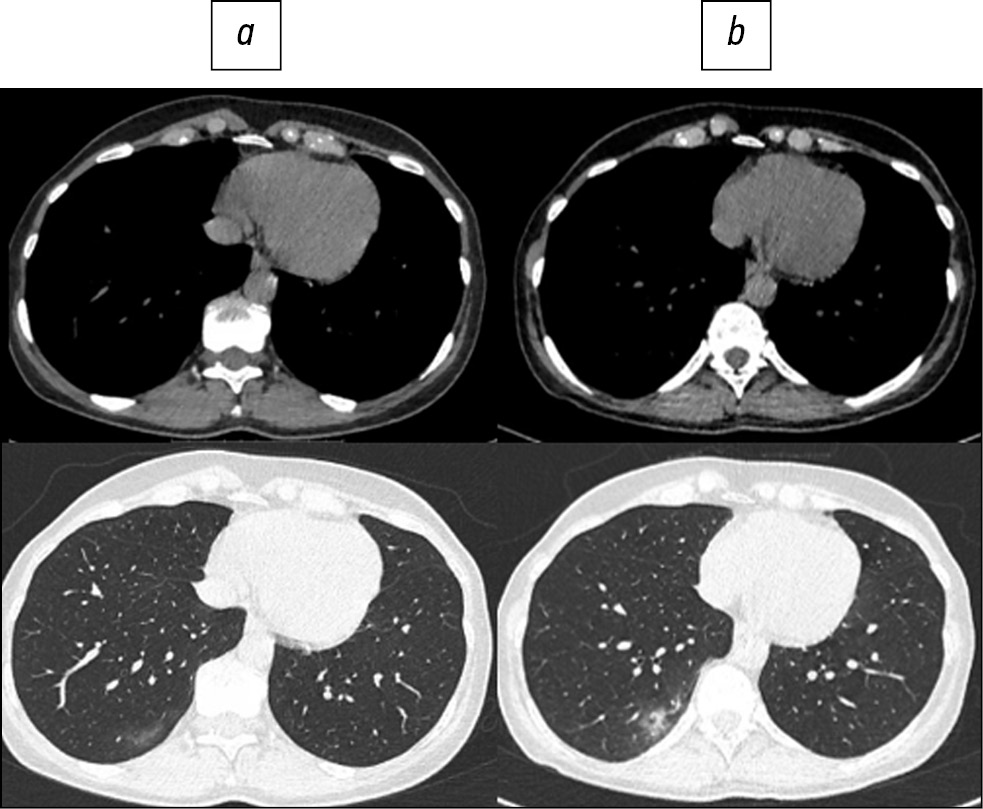

Fig. 1. Patient, 78 years old: standard computed tomography at admission was performed with a radiation load of 2.5 mSv (a), low-dose computed tomography - 1.0 mSv (b).

Here are illustrative examples of clinical cases (Figs. 1–6), demonstrating the similarity of diagnostic value of two aforementioned research methods. Columns on the left (a) show images of a standard CT scan performed upon admission of the patient to the hospital, and columns on the right (b) present LDCT over time. The top line of images indicates the pulmonary window mode, whereas the bottom line indicates the mediastinal window mode. For comparison, values of radiation exposure in each case are presented. Time intervals between standard CT and LDCT were 2–7 days; thus, the primary endpoint was reached in all patients enrolled in the study.